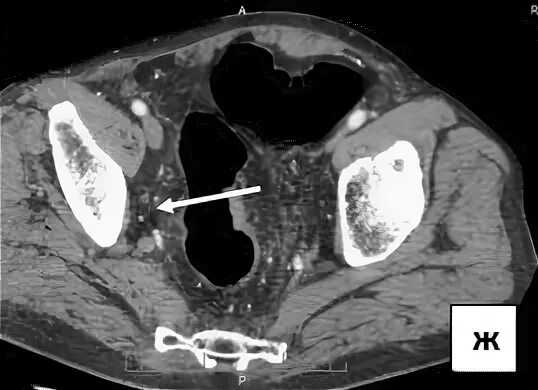

Рак прямой кт